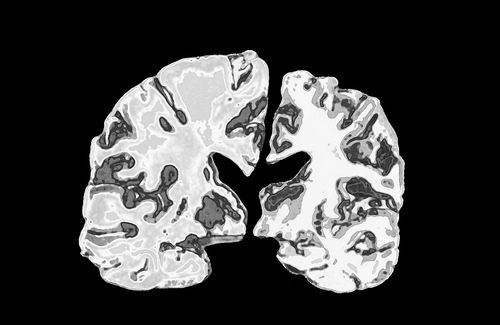

正常人大腦切片(左)與阿爾茨海默病患者大腦切片的對(duì)比。圖片來源:Jessica Wilson